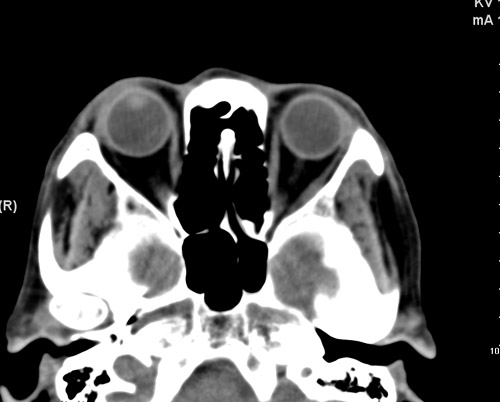

标题: CT17755:女,74 左鼻旁肿胀半年,临床以左上颌窦旁占位行CT [打印本页]

标题: CT17755:女,74 左鼻旁肿胀半年,临床以左上颌窦旁占位行CT

ct考虑鼻前庭囊肿 或鼻翼基底部慢性炎症,左上颌窦少许炎症 请指教

1)考虑左侧鼻前庭囊肿并感染。2)双侧上颌窦炎。

左侧鼻前庭囊肿并感染。双侧上颌窦炎。支持